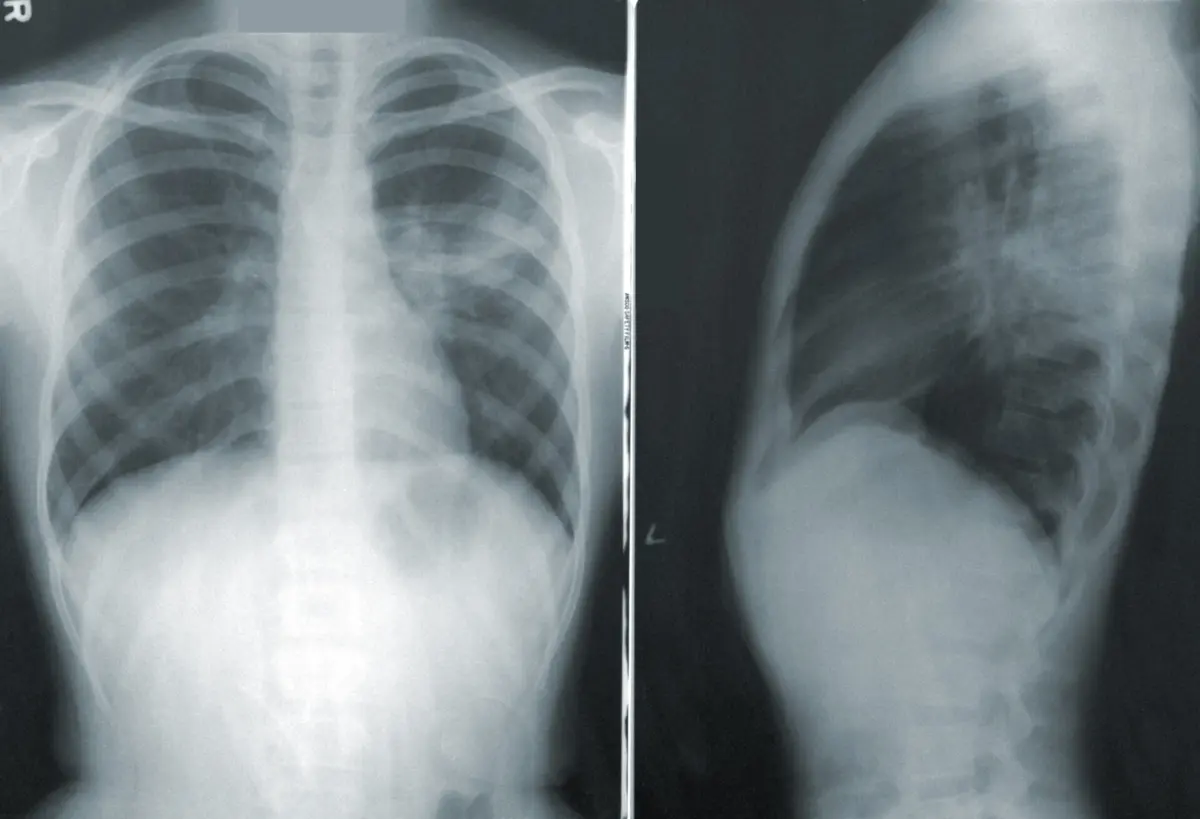

As doenças respiratórias foram responsáveis pela morte de 10.255 portugueses em 2021, menos 988 do que em 2020, segundo o Observatório Nacional das Doenças Respiratórias (ONDR), divulgado esta quinta-feira, que destaca a manutenção das mortes por cancro do pulmão.

No relatório, que cita dados da Administração Central dos Serviços de Saúde (ACSS), é destacada a diminuição das mortes por pneumonia bacteriana, mas também a manutenção das mortes por cancro do pulmão.

De acordo com a síntese enviada à agência Lusa, "as doenças respiratórias continuam a ser uma das principais causas de morbilidade e de mortalidade em Portugal, apesar de ter sido observado um decréscimo gradual a partir de 2019".

"Em 2021, apenas 8,2% das mortes registadas tiveram origem numa doença respiratória. Esta descida pode estar relacionada com a pandemia de covid-19 e com a mudança de hábitos individuais e de grupo que acarretou, nomeadamente o uso obrigatório de máscara e o confinamento", considera o presidente da FPP, José Alves, citado em comunicado.